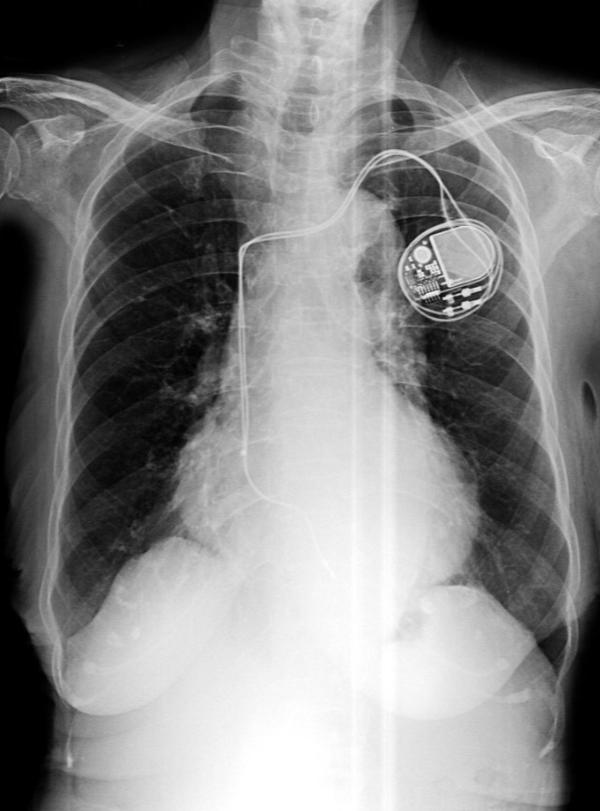

Pacemaker Surgeries Doctors in Katraj for Reliable Heart Rhythm Care